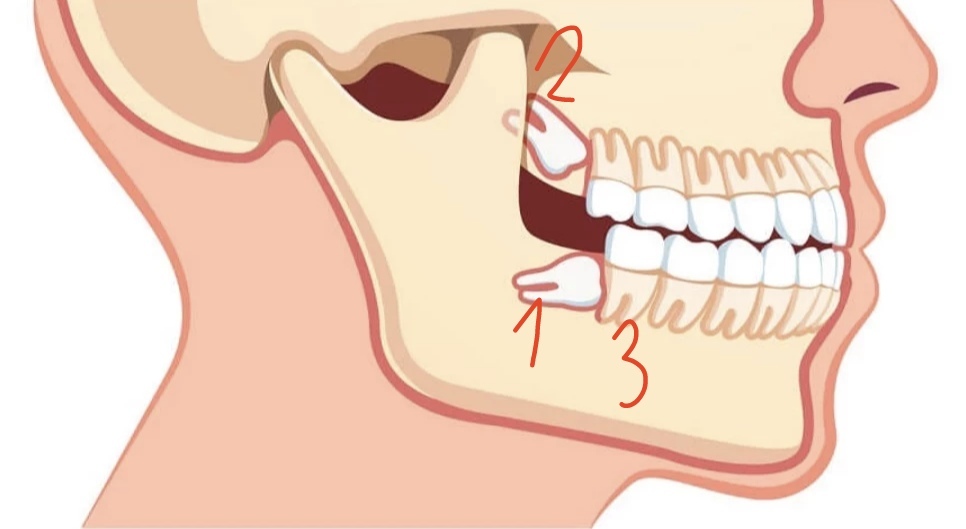

Masz zęba:

1 całkiem zatrzymanego

2 częściowo zatrzymanego

3 rosnącego normalnie ?